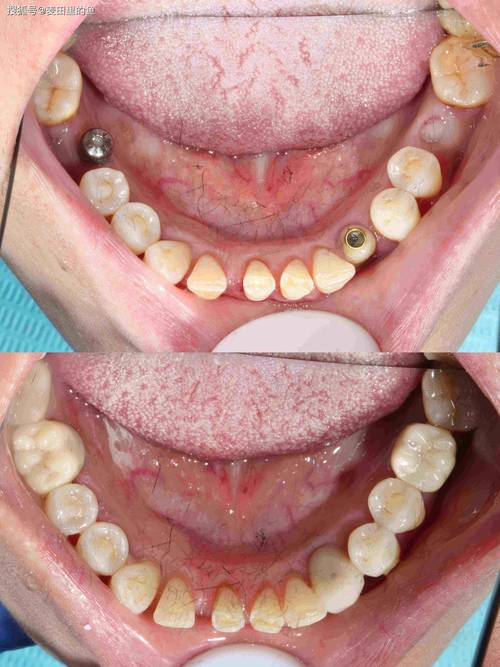

即刻种植时骨量不足者

为缩短缺牙时间,部分患者选择“拔即种”(拔牙后立即种植),但若拔牙窝骨壁不完整(如邻牙倾斜导致骨壁缺损)、骨量不足或存在感染,需同期植骨填充间隙,提高种植体初期稳定性。